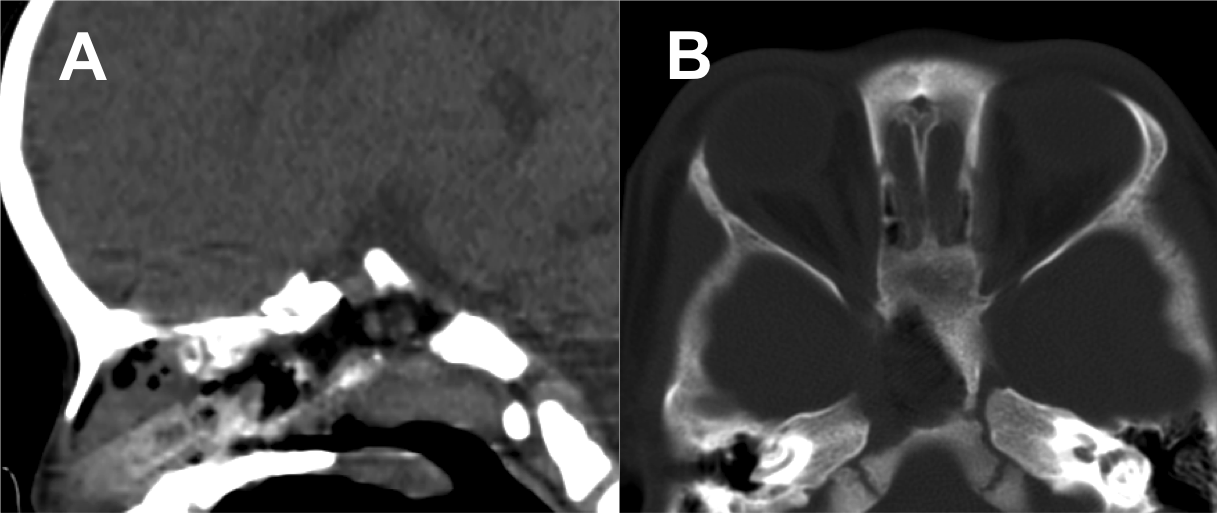

Resultados: Fueron intervenidos 8 pacientes entre los 2 y 14 años, con una edad promedio de nueve años y un seguimiento promedio de 16 meses. En el 75% se hizo una resección total del tumor. Un paciente requirió una reintervención y un paciente fue sometido a radiocirugía post-operatoria. 1 paciente falleció a pesar de múltiples intervenciones, quimioterapia y radioterapia.